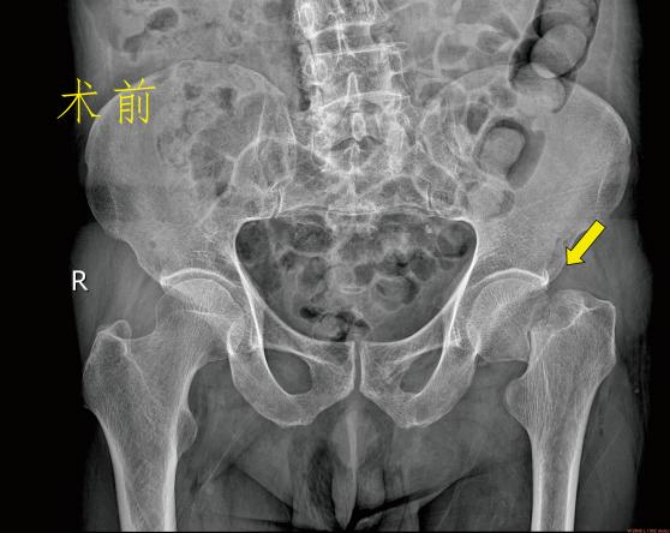

保守治疗 一般说的是卧床、牵引固定,等待骨折自己愈合。费用看似低廉,不用开刀出血,感觉上好像很安全,但老年人由于年纪大、体质差、新陈代谢水平低等原因,发生骨折后的愈合时间较长,所以保守治疗的缺点更多: 2.卧床时间长:髋部由于位置特殊,不像上肢骨折一样可以夹板石膏固定而不影响日常活动,一般髋部骨折通常要床边牵引制动2~3个月甚至更长,吃喝拉撒都在床上。看似很安稳,其实对于患者来说很痛苦。 3.并发症多:长期卧床容易产生褥疮;坠积性肺炎。泌尿系感染、深静脉血栓形成等,严重者危及生命。 4.治疗效果欠佳:单纯的牵引治疗很难保证复位质量。多数患者的骨折容易畸形愈合甚至不愈合,下肢短缩跛行,影响以后的生活质量。 5.加重骨质疏松:长期卧床、制动、骨量大量丢失,使原本的骨质疏松更加雪上加霜。 手术治疗 股骨颈骨折根据骨折移位情况,患者身体状况、年龄、预期寿命等因素,选择空心钉内固定术、人工半髋关节置换术或全髋关节置换术。股骨粗隆间骨折,一般采用闭合复位防旋髓内针内固定术或人工髋关节置换术。股骨粗隆下骨折主要是切开复位髓内针内固定术,很少使用钢板内固定术。 虽然老年髋部骨折术后死亡率高,国内外对其治疗方式争论不断,但研究表明。手术在降低死亡率、并发症发生率方面有明显优势。选择合适手术方式治疗老年髋部骨折可有效的降低死亡率、并发症发生率、改善患者生存质量。真正提高他们的生活质量。 更有多个研究发现,老年髋关节周围骨折的病人采取保守治疗之后的一年内死亡率接近50%!长期卧床引起的并发症,不管是褥疮、血栓、坠积性肺炎还是各种感染,都有可能会是致命的,这才是导致患者死亡的根本原因。 对此我们建议:在符合手术指征的前提下,老年髋部骨折应优选手术治疗。 九江市第一人民医院开发区分院/朱挺平